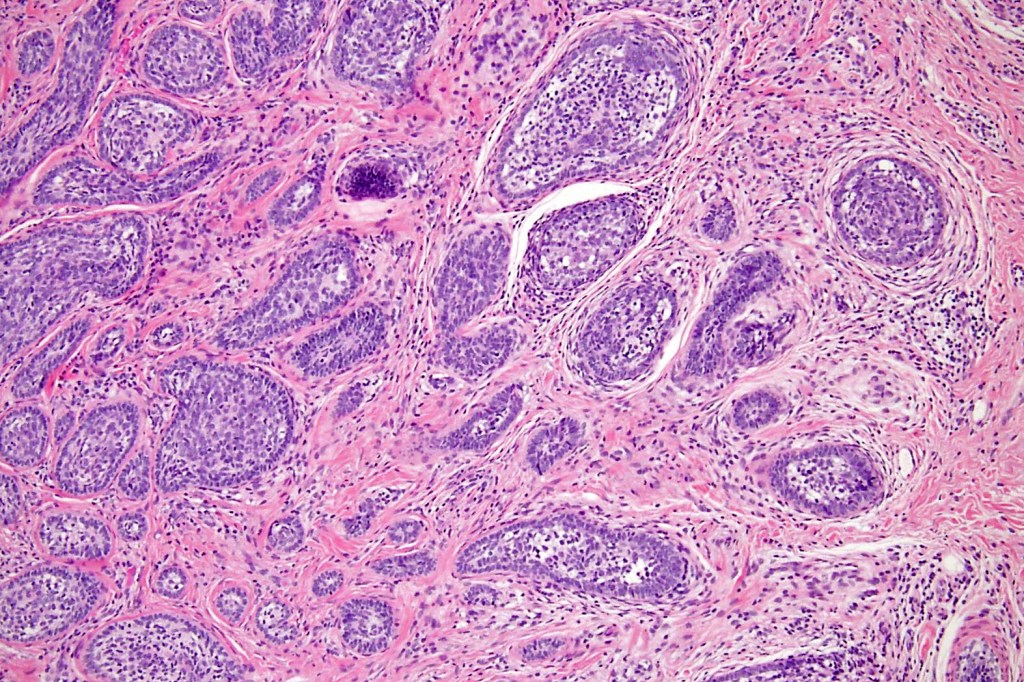

Histological features

•Dermal nodule, rarely extends into subcutaneous fat

•Irregular lobules of epithelial cells embedded in a dense fibrous stroma

•Peripheral rim of darkly staining basaloid cells surrounding larger pale staining cells with vesicular nuclei with often prominent eosinophilic nucleoli

•Central cells PAS positive (glycogen)

•No pleomorphism or mitotic activity

•No retraction artifact or stromal mucin

•Admixed lymphocytes (an obligatory feature)

•Germinal centers sometimes present